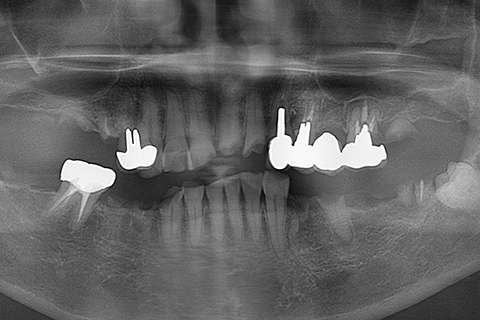

症例1

- 年齢・性別

- 55歳女性

- 治療期間

- 2ヶ月

- 抜歯

- なし

- 治療費

- 66万円

- 備考

- 右下6.7欠損

- 治療内容

- 右下6.7欠損部にインプラント埋入

- 施術の副作用(リスク)

- オペによる知覚障害。インプラントによる歯肉炎。インプラント脱落。